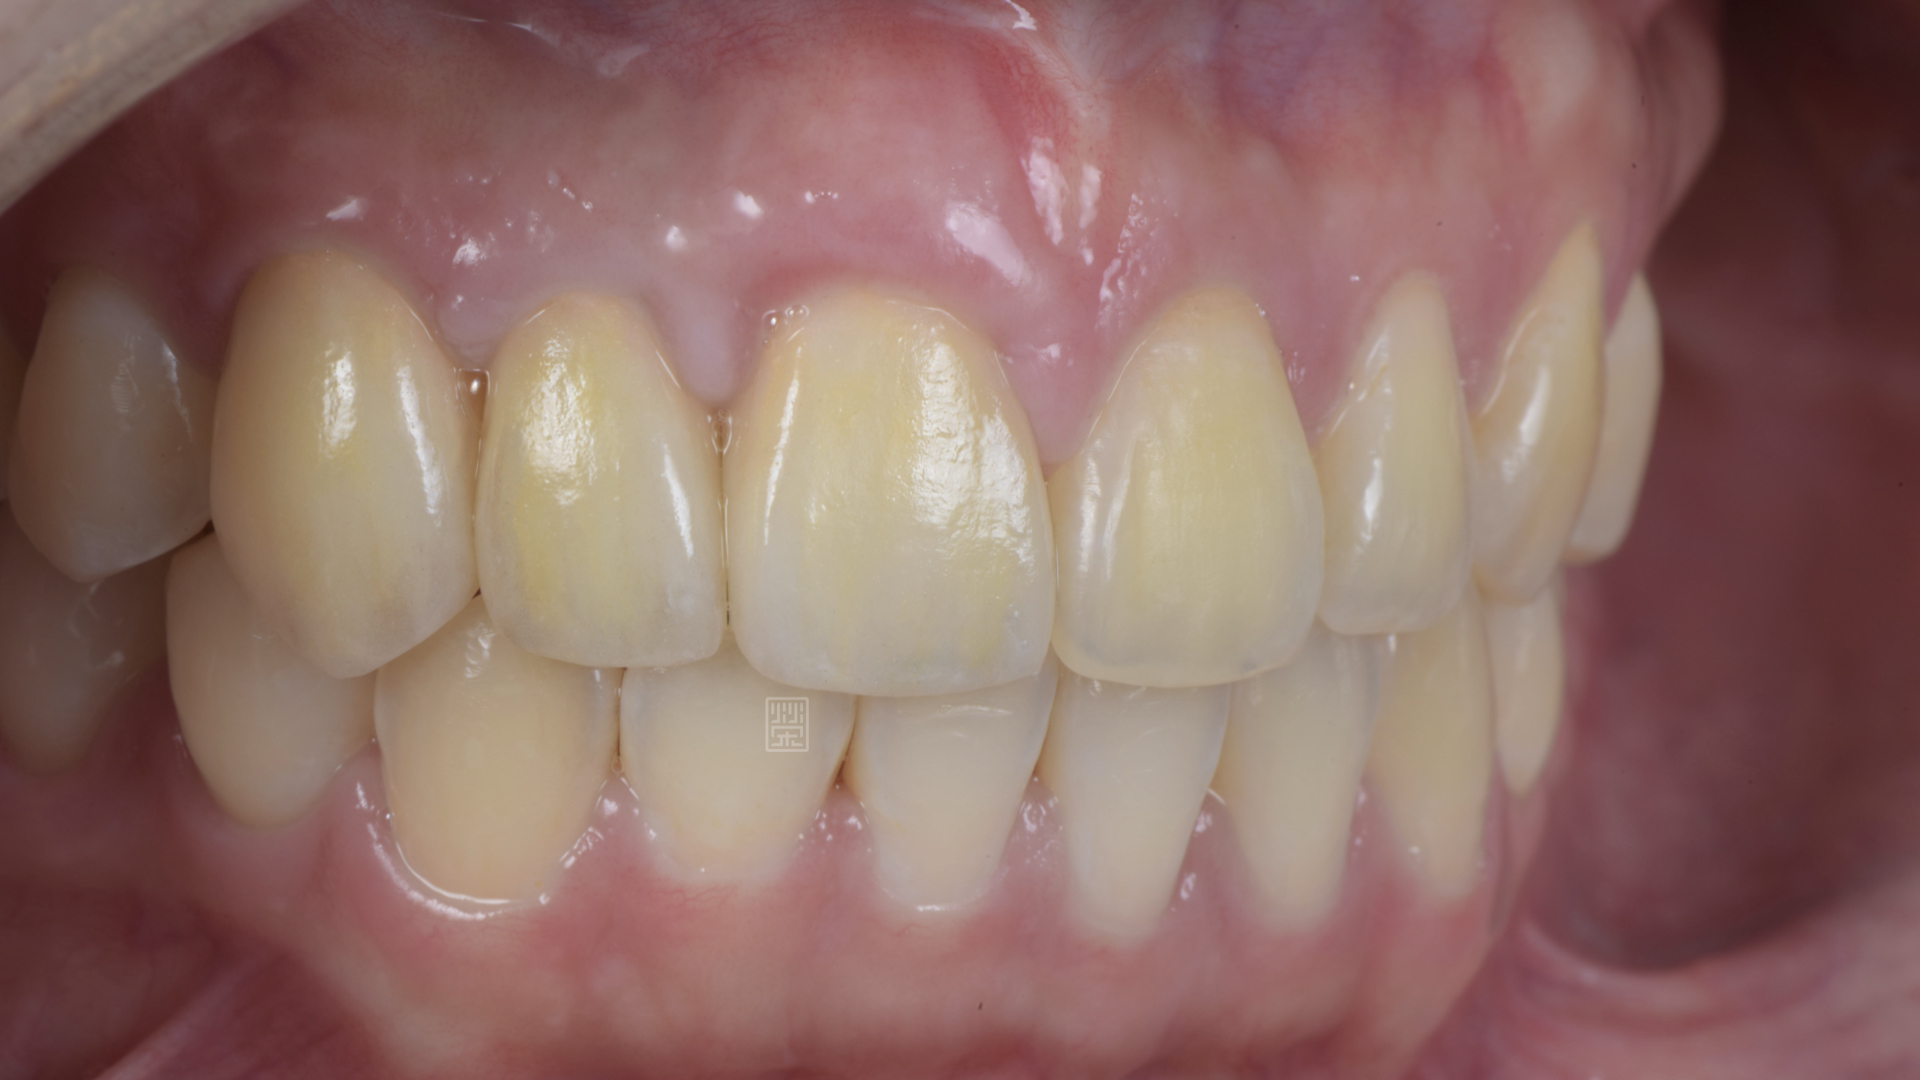

全瓷冠位置、牙齦線位置評估